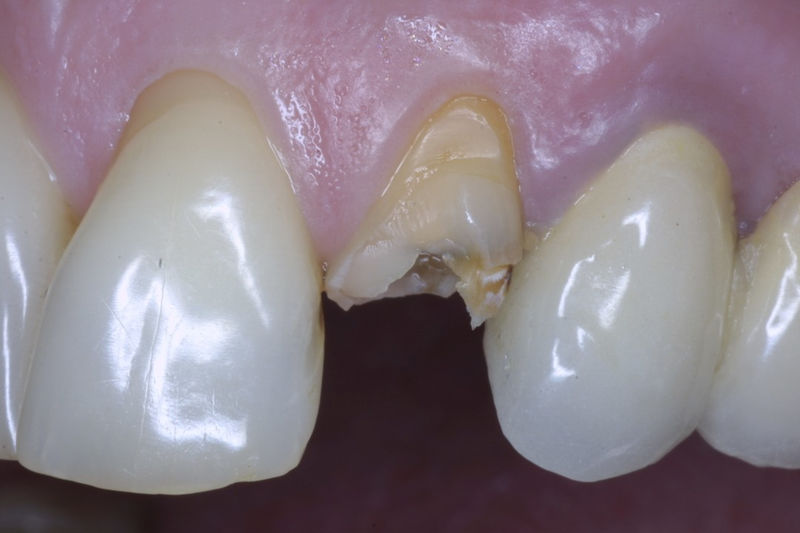

La restauración de un diente tras una endodoncia, es crucial para su supervivencia a largo plazo, ya que el procedimiento puede debilitar la estructura dental. El tipo de restauración elegido depende principalmente de la cantidad de estructura dental remanente después de la endodoncia. Principalmente se usan incrustaciones, coronas y/o postes.

Son aditamentos artificiales colocados en la parte interna de la raíz de dientes con tratamiento endodóntico y con amplia destrucción. Usados comúnmente para soportar coronas completas.